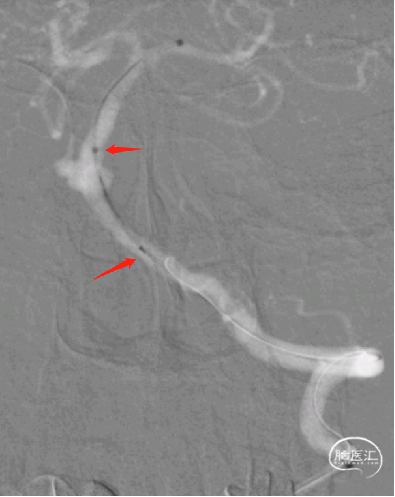

0.014 Synchro微导丝携Fastrack微导管至L-P1,引入4mm*20mm Tubridge血流导向密网支架。

3

Tubridge血流导向密网支架释放,回拉定位,逐步推挤释放支架。